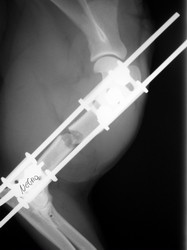

PRÁCTICAS CURSO DE FIJACIÓN EXTERNA PERFECCIONAMIENTO.

Húmero.